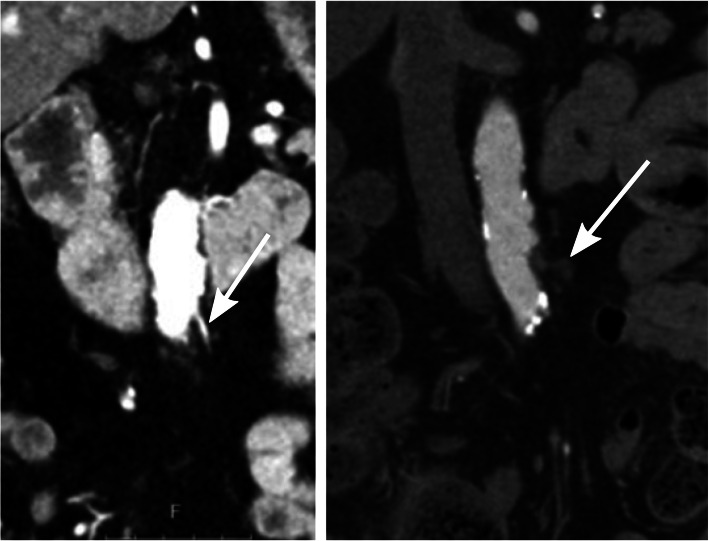

The purpose of the supplementary arterial phase was to map the remaining mesenteric arterial anatomy in order to visualize whether the level of ligation of the IMA was located proximal or distal to the left colic artery. Intra-individual comparisons of the preoperative CT examinations were sometimes used to aid the evaluation. The level of ligation was determined as low if the left colic artery was preserved and high if it could not be identified (Figs. 1 and 2).

Fig. 2.

High ligation level where the inferior mesenteric artery preoperatively can be seen (the image to the left) and postoperatively where it cannot be found (the image to the right). The arrow in the postoperative image to the right demonstrates typical postoperative changes following division of the inferior mesenteric artery close to the aorta